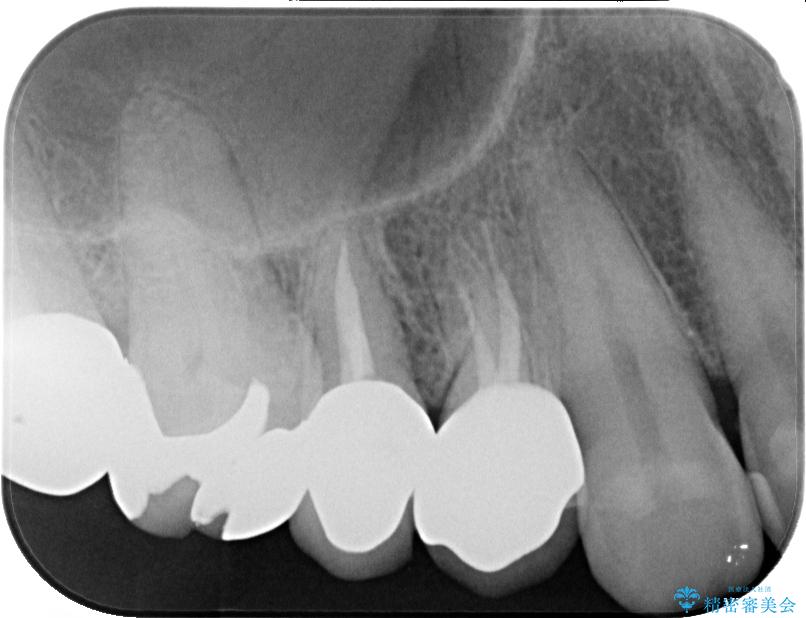

• 自然な美しさと強度を両立!右上小臼歯の被せもの脱離に対する審美補綴治療 治療前画像